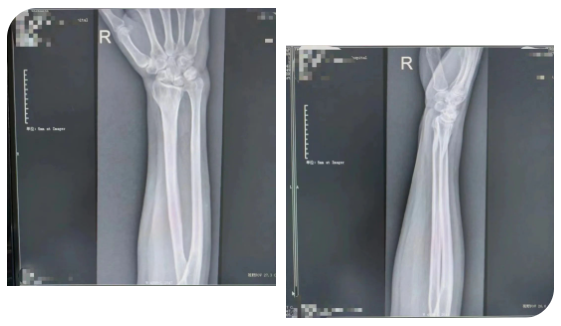

患者于门诊善相关检查后诊断为:右侧尺骨撞击综合征。创伤外科主任医师王磊及其团队在仔细评估后,经过周密的术前准备,在臂丛麻醉下行“右侧尺骨短缩截骨”。该术式通过恢复中立或负向的尺骨变异来解压尺腕关节从而缓解尺骨撞击症状。